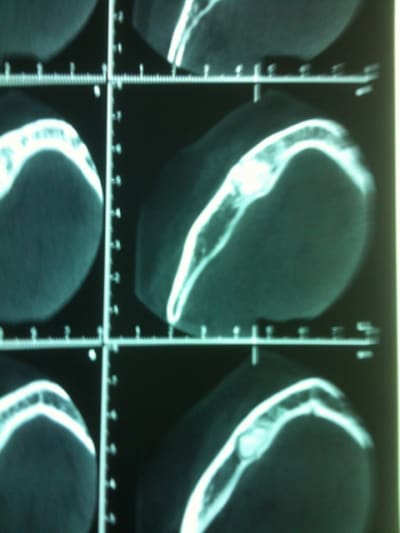

Un confrère savant pourrait il me donner un diagnostic et une CAT concernant le tissu osseux en regard de 45 ?

La racine parait fracturée mais à part une légère douleur à la pression, rien d'autre..

çà semble être une ostéïte condensante...